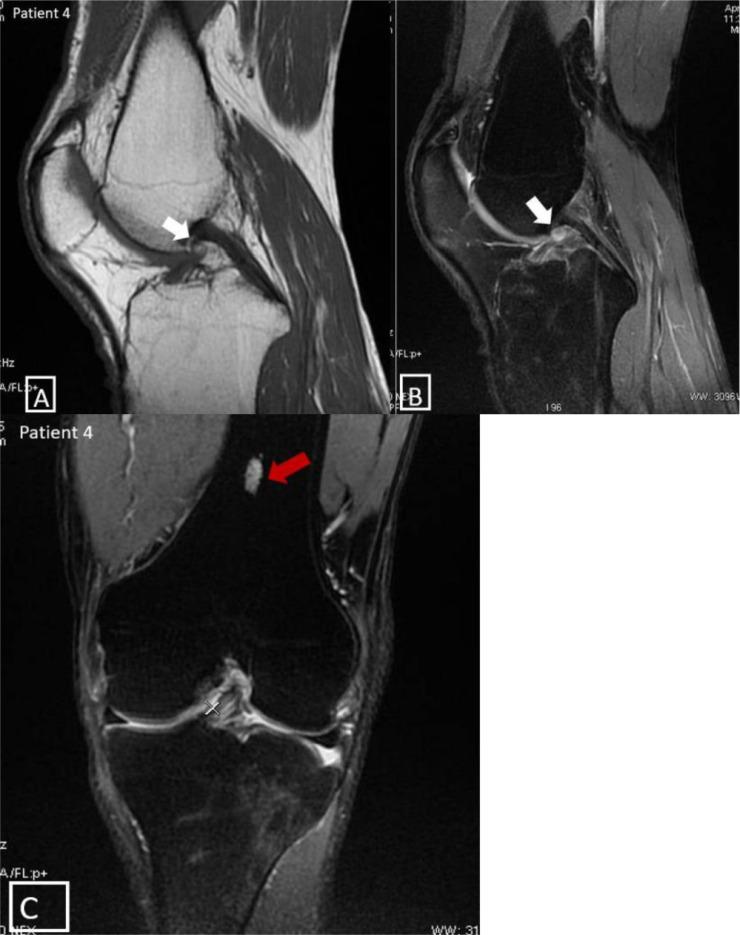

前交叉韧带囊肿:关于一种罕见病症。

Anterior cruciate ligament cysts: About a rare condition.

The purpose of this study was to provide information on cysts of the anterior cruciate ligament (ACL) of the knee. This included an anatomical and radio-anatomical reminder of the cruciate ligaments of the knee, along with details of the epidemiology, etiopathogenesis, anatomical risk factors, clinical presentation, differential diagnosis, and treatment of ACL cysts. A retrospective analysis was conducted, involving the review of 7 radioclinical records from the medical imaging department of Ibn Sina University Hospital in Rabat, covering a period of 3 years (2018-2020), during which 7 cases of ACL cysts were diagnosed. The results revealed that ACL cysts are a rare condition, frequently detected incidentally during the assessment of meniscal lesions. Symptoms commonly include knee pain and limited mobility, and MRI is considered the diagnostic modality of for distinguishing between simple fluid-filled cysts and infiltrative cysts, as well as for ruling out other differential diagnoses. Treatment options include radio-guided infiltration puncture and arthroscopic resection.

摘要